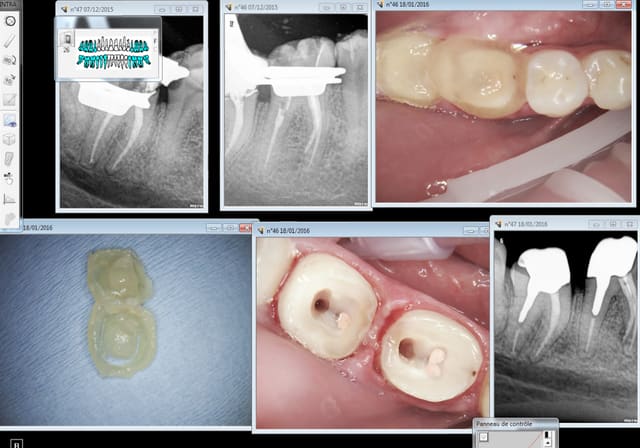

En postérieur le plus rapide c'est le clip flow, imbattable -))))

Capture d e cran 2016 01 18 12.49 - Eugenol

Pratique pour la pose gencive maintenue à distance. dépose avec un coup de sonde, rien à nettoyer.

Capture d e cran 2016 01 19 10.09 - Eugenol